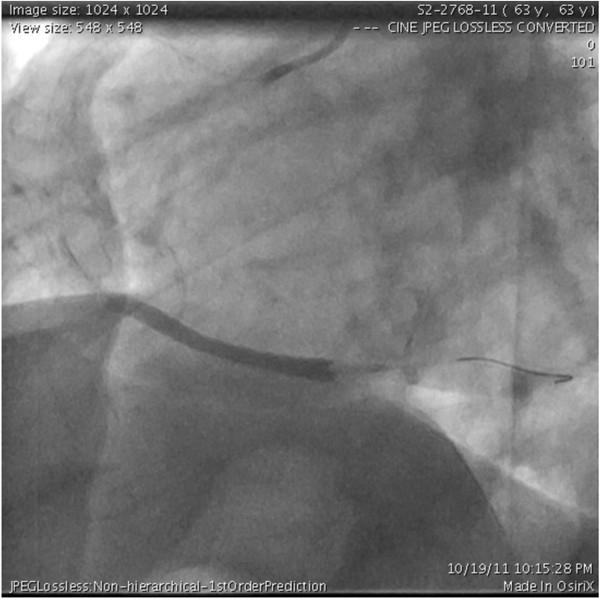

Ischemic rupture of the anterolateral papillary muscle is uncommon due to its dual blood supply. It usually follows an ischemic event involving branches of the left circumflex or left anterior descending arteries. We present a case of a patient admitted with an acute inferior wall myocardial infarction and an isolated distal right coronary artery occlusion. Acute mitral regurgitation with rupture of the anterolateral papillary muscle was diagnosed on the fifth post-infarction day. The patient underwent mitral valve replacement and coronary artery bypass grafting to the posterior descending artery. We conclude that anterolateral papillary muscle rupture may also result from an isolated right coronary lesion.